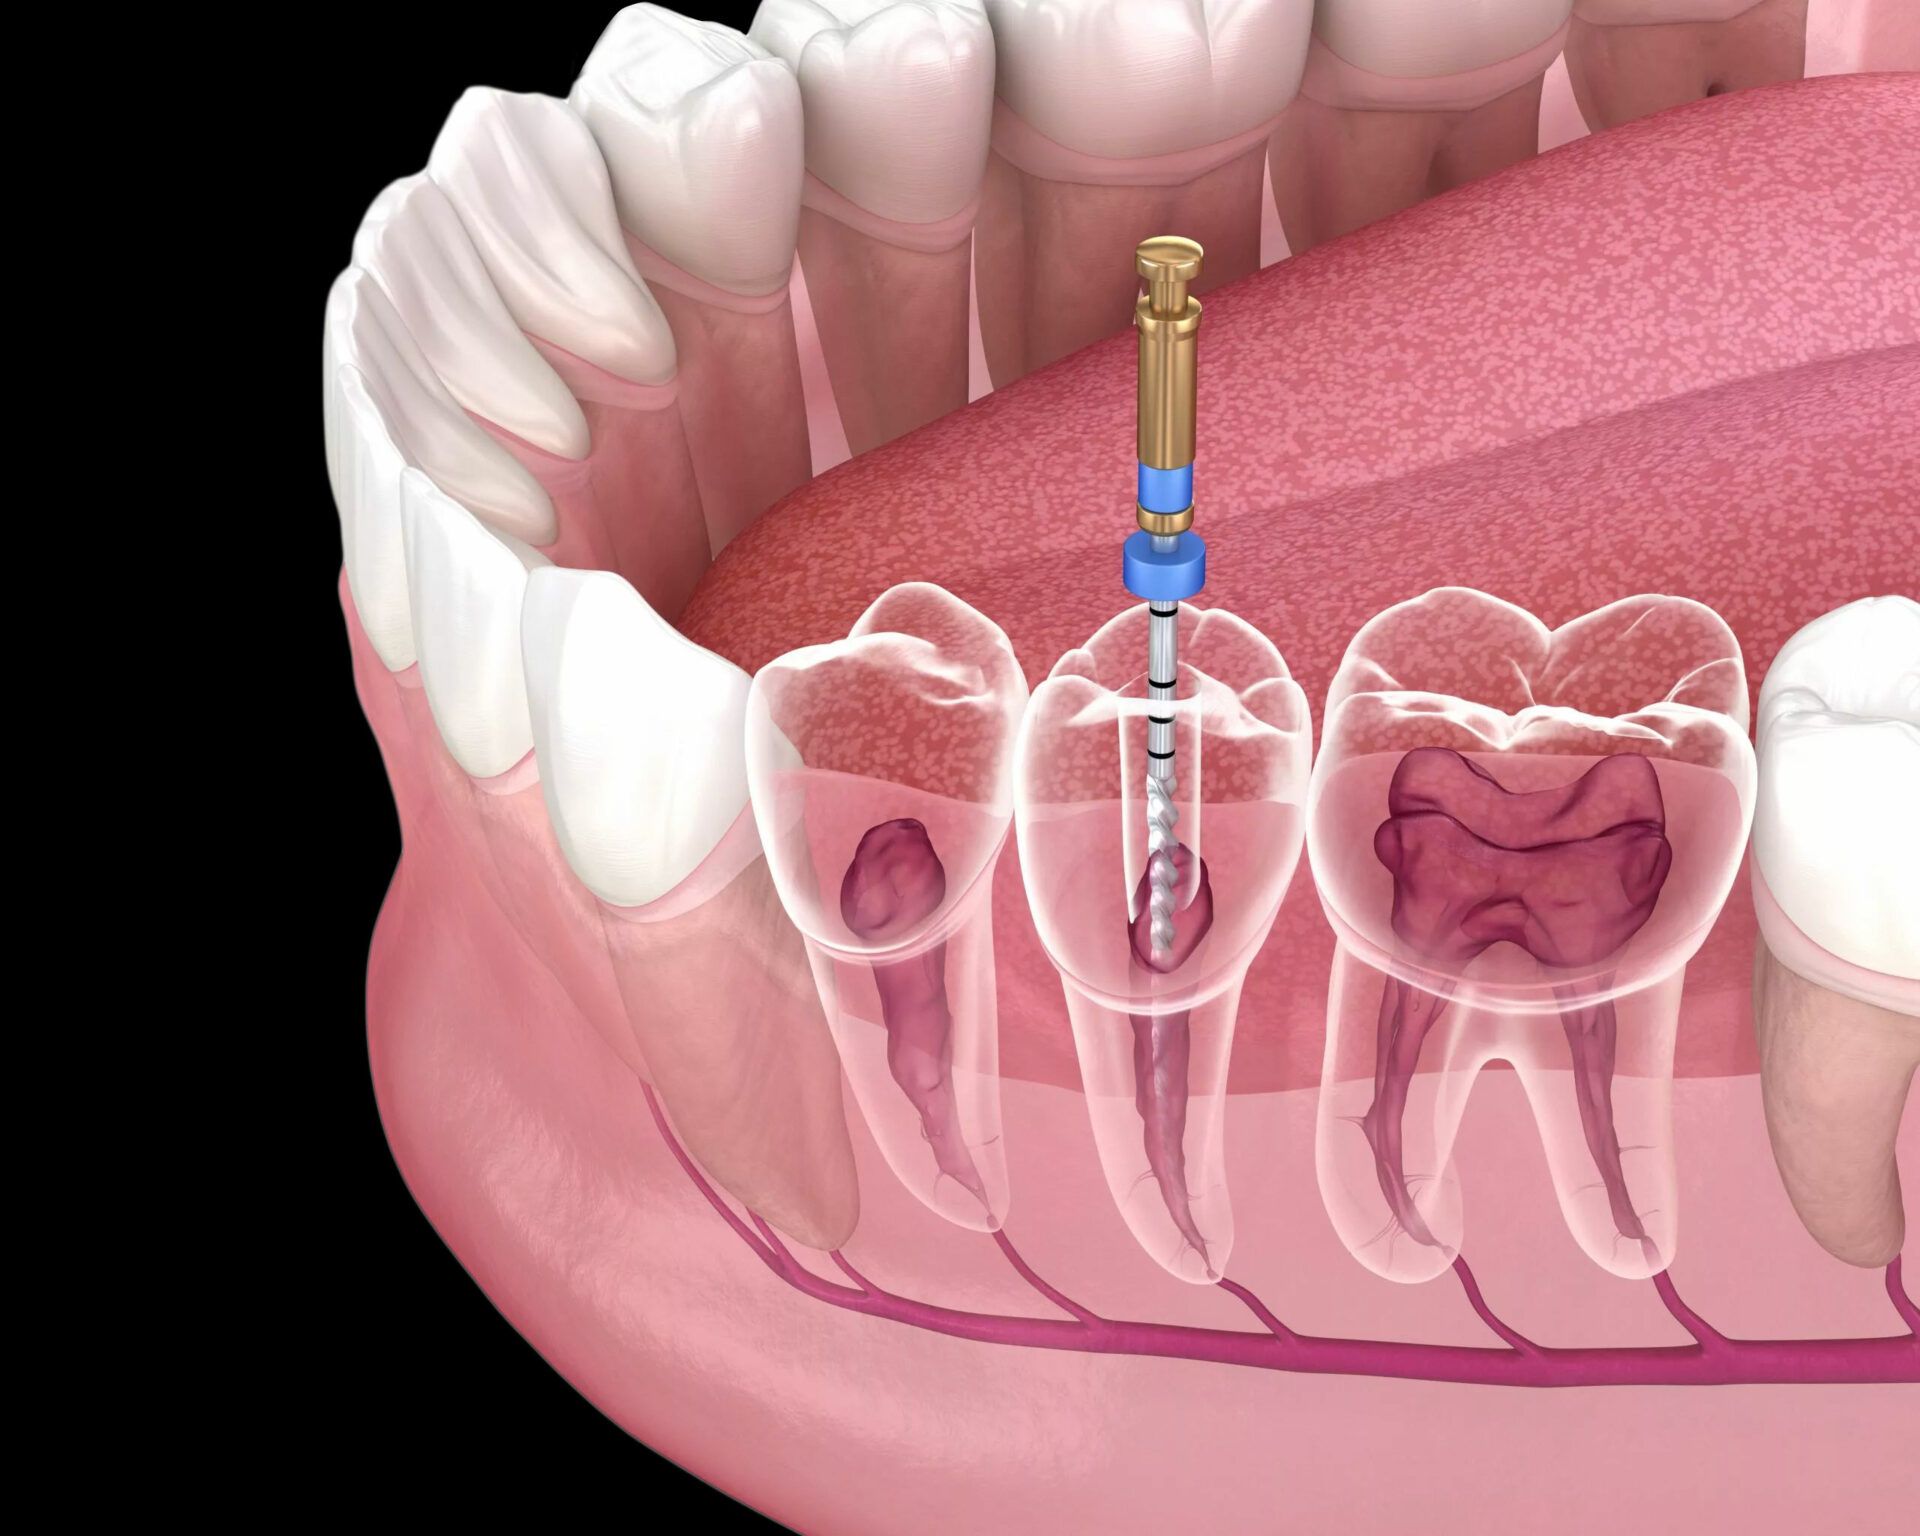

A root canal treatment in Dubai is a dental procedure used to save a tooth that’s infected or badly decayed. It involves removing the inflamed pulp inside the tooth, cleaning the canals, and sealing them. This procedure helps stop pain, prevents further infection, and preserves your natural tooth.

According to holistic dental experts, the tooth may appear “dead” after a root canal. Though sterilized and sealed, microscopic bacteria may still survive in the dentinal tubules, potentially leading to low-grade infections that traditional x-rays cannot detect.

Yes—root canal treatment in Dubai is performed with advanced tools and protocols that meet global standards. Clinics use digital x-rays, rotary instruments, and high-quality sealing materials to ensure complete disinfection and minimal post-operative issues.